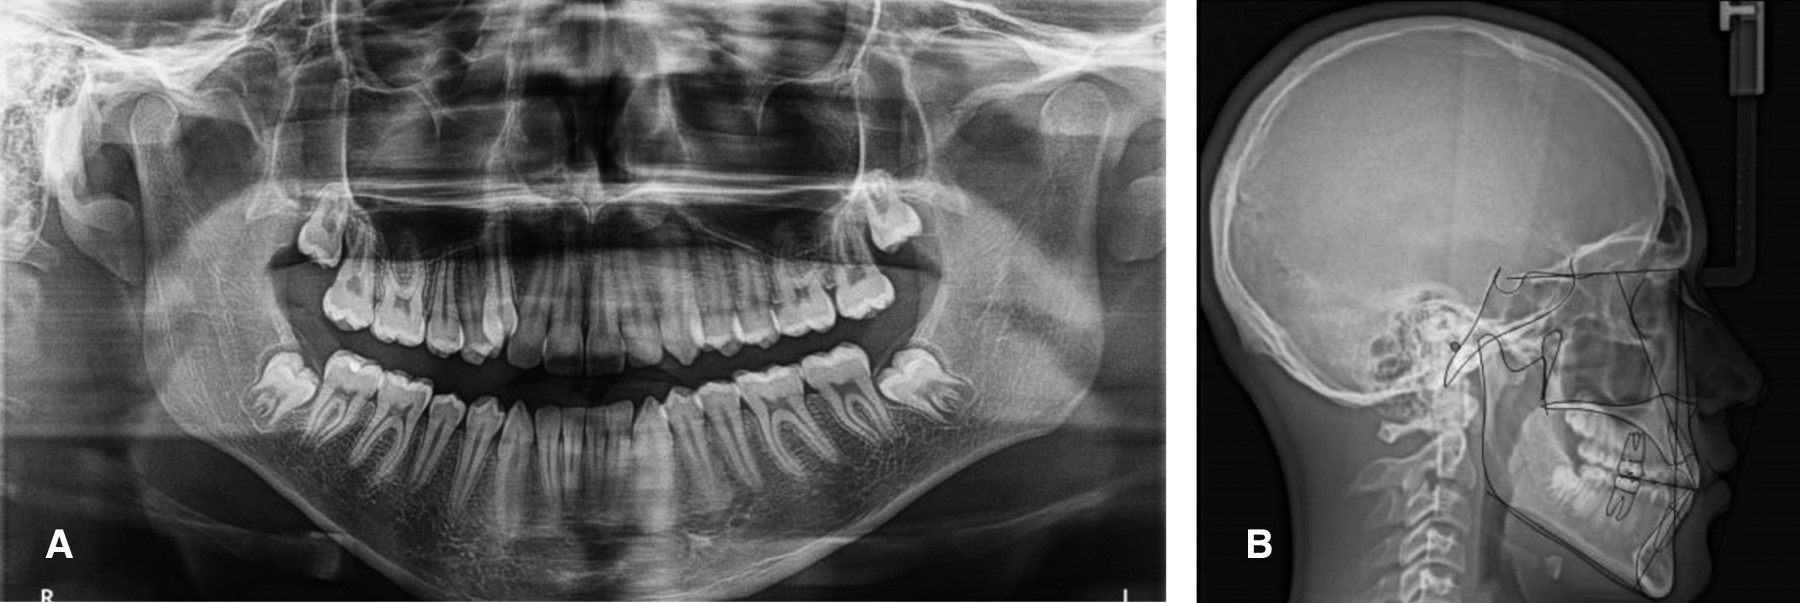

Radiográficamente, en la ortopantomografía se observaron ramas mandibulares simétricas, cóndilos simétricos, niveles de crestas óseas sanas, presencia de gérmenes dentarios de terceros molares en los cuatro cuadrantes, proporción corona-raíz con relación de 1:1 y raíces cónicas (Figura 3A). En la radiografía lateral de cráneo se trazó la cefalometría de Steiner con el software Dolphin Imaging (9.0.00.19©1998-2004 Patterson Companies, Inc.), donde se observó una clase I esqueletal, vías aéreas superiores permeables, perfil recto e incisivos inferiores ligeramente retroinclinados (Figura 3B y Tabla 1).

Figura 3